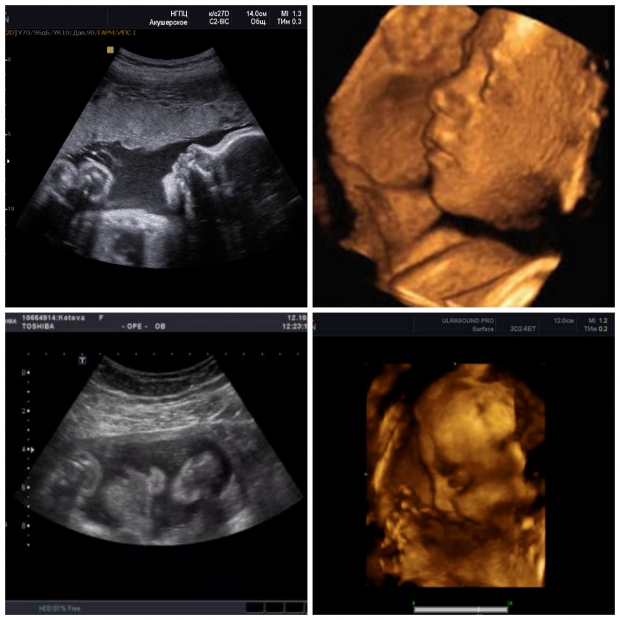

УЗИ: 28 неделя беременности

Начался третий и заключительный триместр беременности. Вес плода уже превышает один килограмм. На ультразвуковом исследовании специалисты оценивают его размеры и положение в матке. С этой недели малыш начинает занимать ту позицию, из которой, скорее всего, будет рожден. Тем не менее, если на УЗИ врач сообщил, что ребенок находится в неправильном положении, не стоит паниковать — в матке все еще достаточно пространства, чтобы он мог изменить свою ориентацию.